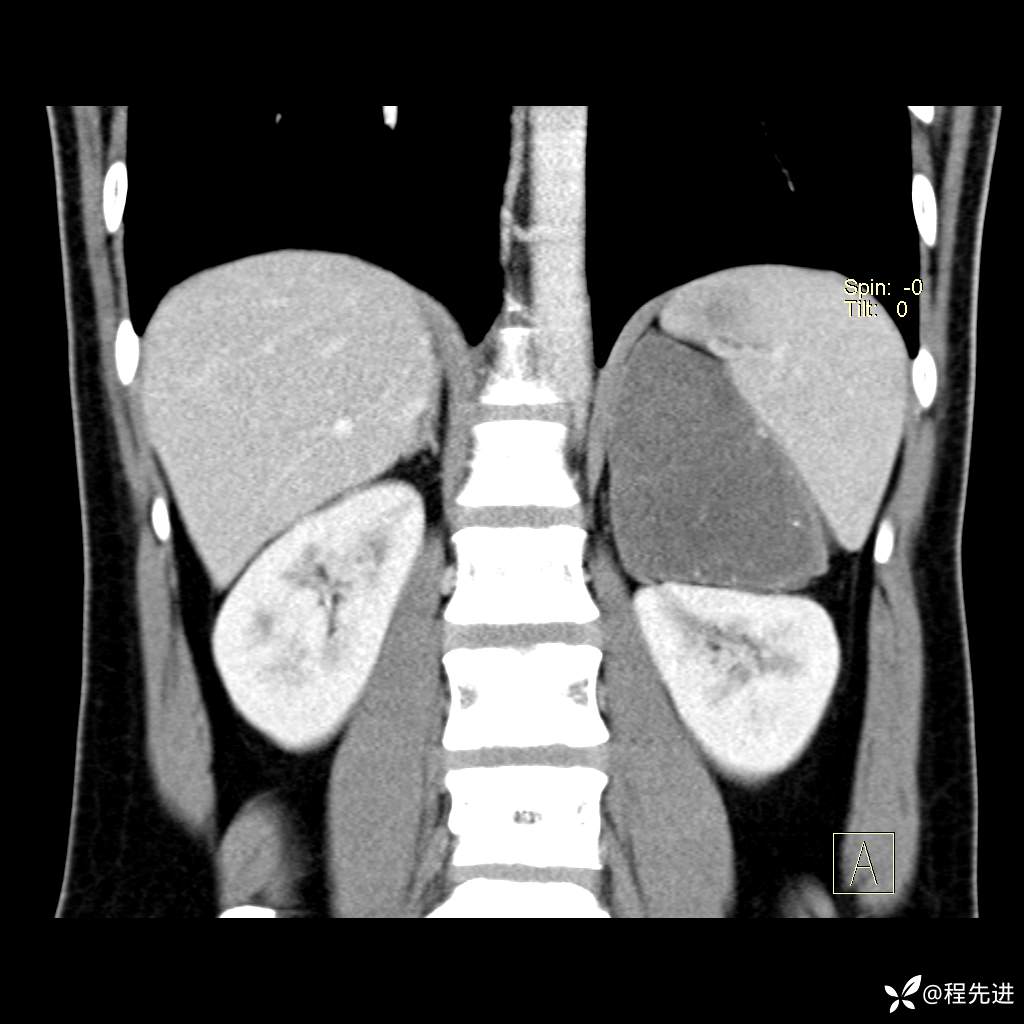

【腹盆】特别精彩病例|体检发现的左侧腹膜后占位期待您的精彩解读

患者年龄:25岁

简要病史:体检发现

CT平扫:(CT值:平扫,27HU,动脉期,27HU,门静脉期,31HU,平衡期,32HU)

冠状位重建: